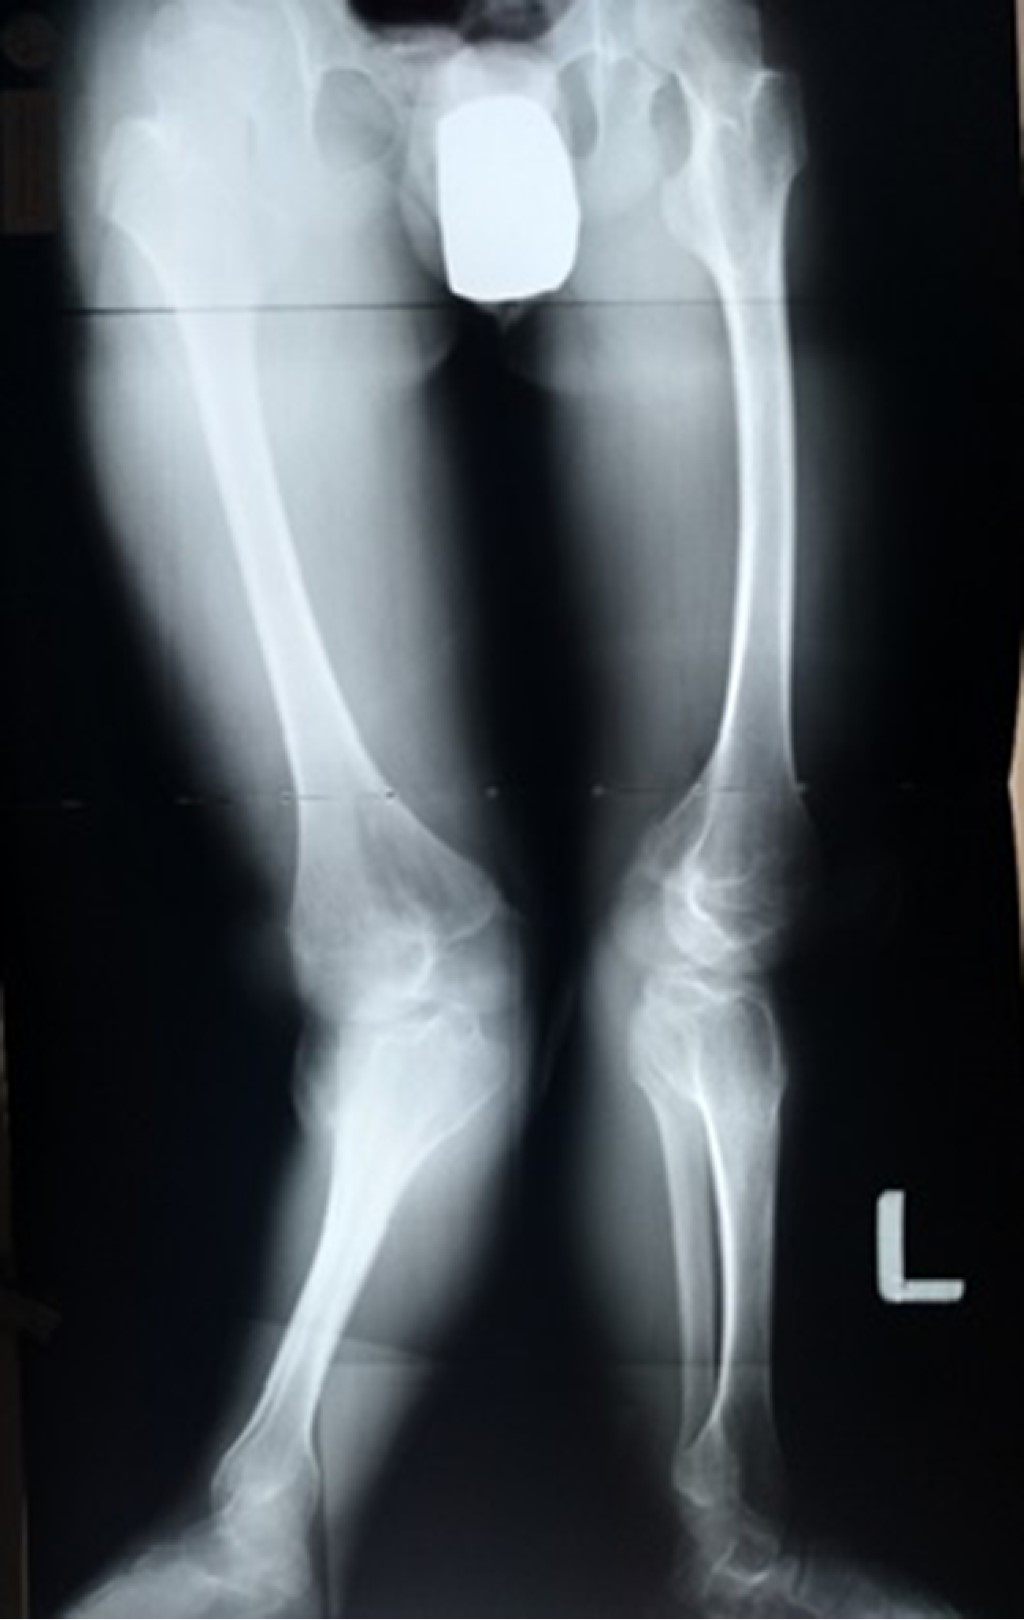

Se realizó la toma de radiografías panorámicas y segmentarias para una mejor planeación quirúrgica. Se encontró una depresión articular a nivel de plataforma tibial lateral bilateral, con valgo de rodillas de 44o derecha y 48o izquierda. Una MAD (desviación del eje mecánico) de 130 mm derecho y 122 mm izquierdo (Figura 1).

Figura 1